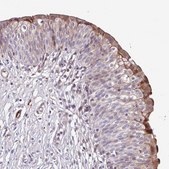

• IHC tissue array of 44 normal human tissues and 20 of the most common cancer type tissues.

We previously reported an accurate urine-based bladder cancer (BCa)-associated diagnostic signature that can be used to non-invasively detect BCa. In this study, we investigated whether a component of this signature could risk stratify patients with BCa. Utilizing immunohistochemistry, we investigated

To validate the expression of a urine-based bladder cancer associated diagnostic signature comprised of 10 targets; ANG, CA9, MMP9, MMP10, SERPINA1, APOE, SDC1, VEGFA, SERPINE1 and IL8 in bladder tumor tissues. Immunohistochemical analyses were performed on tumor specimens from 213